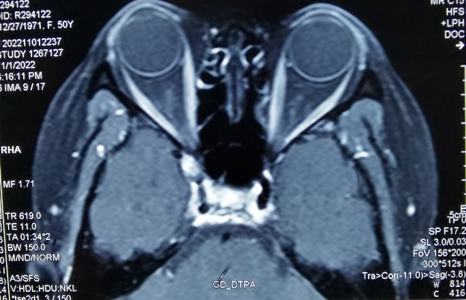

? ? ? 今年40歲的王女士家住江蘇,2個月前發(fā)現(xiàn)自己右眼看什么東西都有點模糊,去醫(yī)院檢查發(fā)現(xiàn)裸眼視力0.4,沒什么問題。后面回到家里發(fā)現(xiàn)右眼越來越看不清了,又跑到江蘇當(dāng)?shù)氐尼t(yī)院檢查,診斷為“白內(nèi)障”,并做了白內(nèi)障手術(shù),但手術(shù)后視力沒有一點改善。

? ? ? 輾轉(zhuǎn)南京、上海、北京等地四處求醫(yī),最終被診斷為“顱眶溝通性眼眶腫瘤”,王女士這才知道,原來一切都是因為眼睛里長了一個腫瘤!本以為找到病灶做手術(shù)就好了,沒有想到的是,竟然沒人敢給王女士做這個手術(shù)!